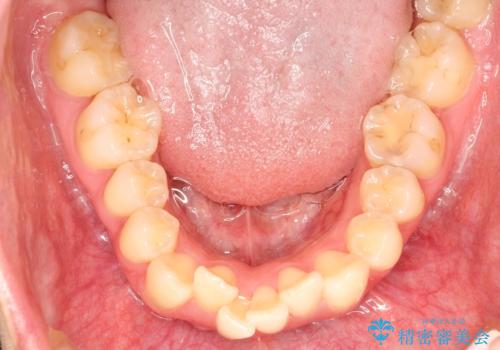

抜歯矯正により、前歯をしっかり下げることで口元がすっきりしました。